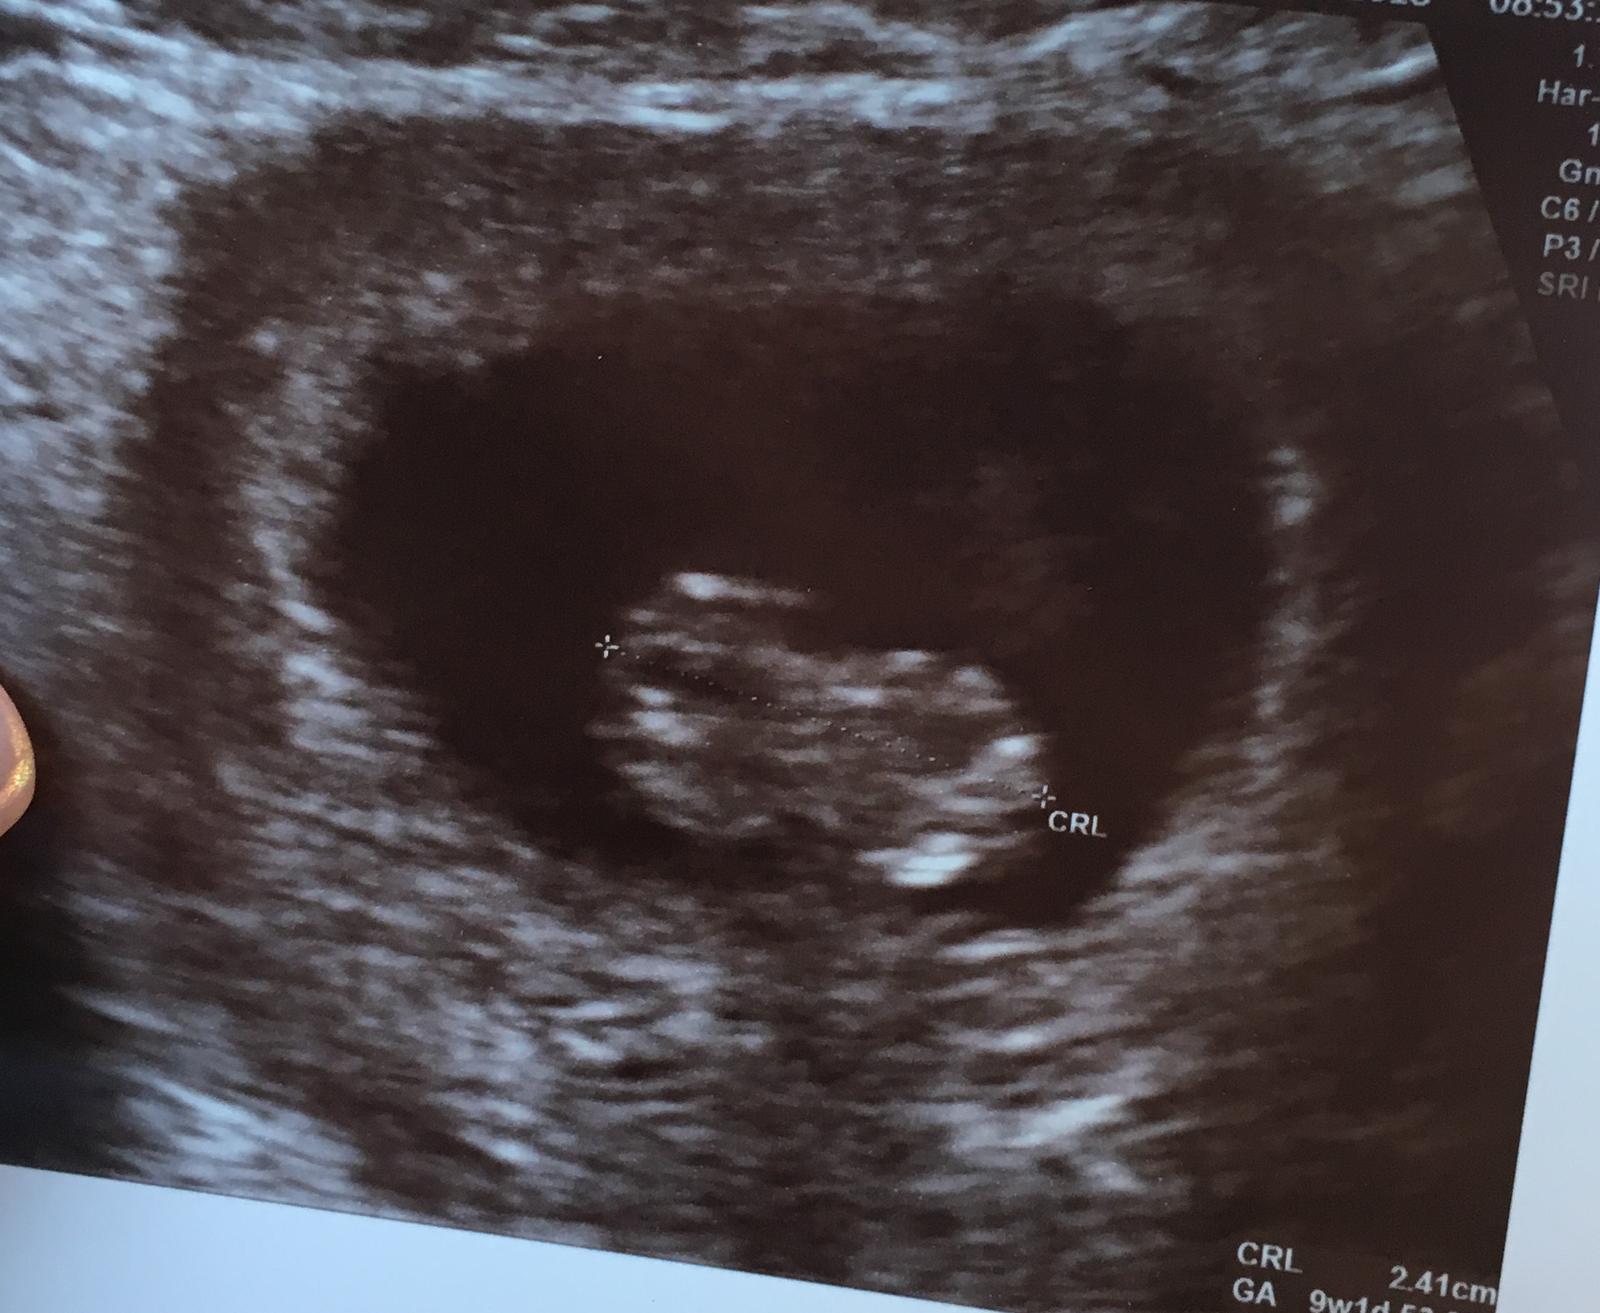

My dnes na ultrazvuku, sme v 8tt a mame 1,11cm. O dva tyzdne dostanem uz aj knizku 😍😍 juuuuuj som stastna a zaroven narasta aj strach o babatko

@nadej2018 uzasneeeee ❤😍 Tesim sa spolu s tebou, drobcek vyzera ako taky Bursky oriesok na fotke 🙂 Gratulujem k tehu knizke, teraz si oficialne v klube tehuliek a uz si to len uzivaj. Si pamatam, ze ja som si kazdy tyzden citala, ako drobcek rastie a co sa deje v brusku. Bolo to krasne.